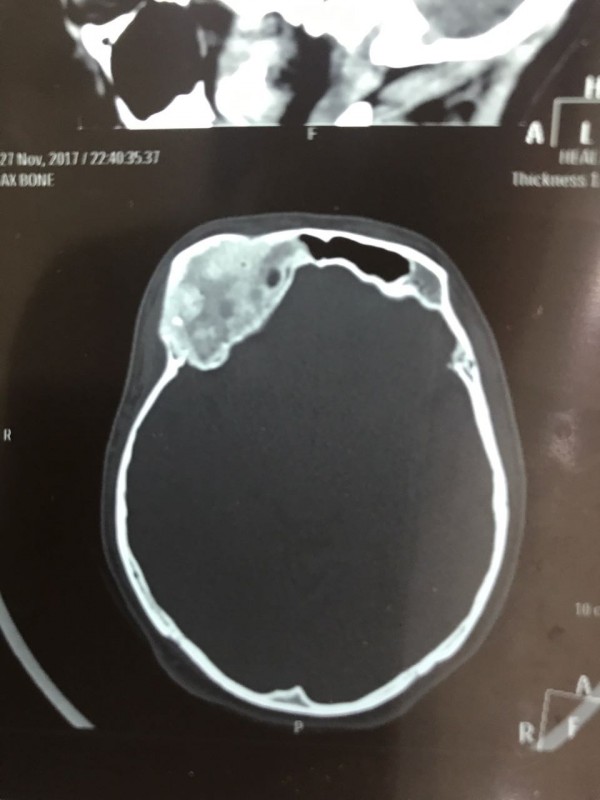

"Компьютерная томография показала, что костная опухоль поражала лобную кость и "крышу" орбиты глаза, которая, в свою очередь, сдавливала глазное яблоко. Чтобы убрать опухоль, потребовалось немало времени. Наша задача была сохранить глазное яблоко, зрительный нерв и сосуды. Если неправильно провести операцию и неправильно закрыть дефект, то в последующем это может привести к эстетической неполноте и асимметрии лица. Уникальность еще и в том, что в операции применялась 3D-стереолитография, которая делается только в Алматы", - рассказал он.

Снимок черепа. Опухоль с левой стороны. Фото предоставлено Константином Ли